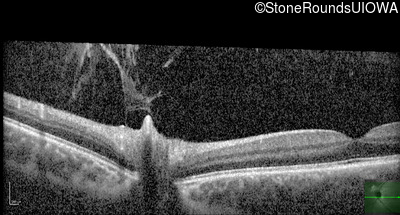

Optical Coherence Tomography - Right - 20/20 -1 sc

Exemplar / OCT Stack

Optical Coherence Tomography - Left - 20/20 -1 sc